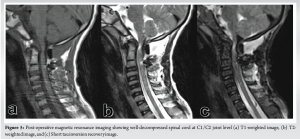

A 14-year-old boy presented to the spine clinic with progressive weakness of the bilateral upper limb, progressing to bilateral lower limb for the past 1.5 years following trivial trauma to the neck and with bowel and bladder incontinence for the past 1 year. At presentation, he was not able to stand without support, had increased tone (modified Ashworth grade 1) in bilateral upper and lower limbs, with functional motor power present and no sensory deficit in any of the dermatomes. On elicitation, both upper and lower limb reflexes were exaggerated. Exaggerated pectoralis reflex and presence of scapulohumeral reflex suggested a clinical diagnosis of supra-axial cervical myelopathy. On further evaluation, special signs such as Hoffman’s sign and grasp-release test were positive. Cervical spine radiograph showed atlantoaxial subluxation with decreased posterior atlanto-dens interval along with fusion of C2 and C3 vertebrae (Fig. 1). On magnetic resonance imaging cervical spine, thecal sac and spinal cord compression at the level of C1/C2 joint with no visible cerebrospinal fluid rim was noted (Fig. 2). 3D Computed tomography angiography (CTA) of the cervical spine showed an incomplete anterior and posterior arch of the atlas with well-corticated bony fragments within the posterior arch defect. Note of fenestration of VA on right side and high-riding VA was also made (Fig. 3). A final diagnosis of supra-axial extradural compressive cervical myelopathy due to congenital atlantoaxial subluxation with anomalous VA (Nurick Grade 5) was made. The patient was planned for C1-C2 reduction and posterior instrumented fusion using C1 lateral mass and C2 laminar screws under intraoperative neuromonitoring. The patient was positioned prone on Mayfield, and a longitudinal midline approach from C1 to C3 was carried out, elevating the paraspinal muscle subperiosteally from the midline. A congenital defect in the posterior arch of C1 was noted. First, the left side C1 lateral mass screw was put after identifying the entry point. On the right side, the aberrant VA was freed from the posterior arch of C1 and retracted, inferiorly exposing the lateral mass of C1 along with facets of C1-C2 joint, and C1 lateral mass screw was inserted. Further, laminar screws were placed bilaterally in C2. C1 was reduced over C2 using rod cantilever mechanism and by applying compression force bilaterally between the C1 lateral mass and the C2 laminar screws. Decompression was achieved by removing the remaining C1 posterior arch and corticated bony fragment from the midline. Harvested local bone autograft was placed in the C1-C2 joint on the left side and the prepared fusion bed posteriorly (Figs. 4 and 5).

Gait training was started, and post-operative neurological assessment showed normal tone in both upper and lower limbs at 6 weeks. At 6 months, the patient started walking with support and had complete recovery of bowel movements and partial recovery in bladder sensations. At final follow-up of 18 months, the patient is walking independently (Nurick Grade 2). The patient has returned to his routine daily activities with no motor deficit in bilateral upper and lower limbs (Fig. 6).